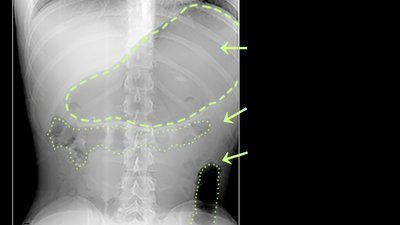

Retrograde Cricopharyngeus Dysfunction (R-CPD) is a condition where the cricopharygneus muscle located at the bottom of the throat doesn’t relax to allow gas to pass upwards- preventing the burping response. Treatment of this condition involves botox injections into the cricopharyngeus muscle which costs a lot for Canadians as only two physicians offer the treatment, one in the UK and one in the US. Thousands of people live with this condition but are unaware that there is such a condition, due to it not being recognised by GPs and medical professions. They instead live their daily lives in pain and discomfort, misdiagnosed with IBS or GERD. I myself live with this condition but was told by GPs that it was nothing to be concerned about. After doing plenty of research online, I found many individuals across the globe suffer from this condition just as I have for my entire life, many of which use the term no-burp or no-burpers. I am hoping that this petition can help to spread awareness of R-CPD as the more awareness there is about it, the more people will speak up, including sufferers of the condition. The more people speak up about it, the more common it will be. This hopefully will lead to more recognition and then correct diagnoses from GP’s and other professions. This ultimately should enhance the chance of the botox treatment being made available in Canada and covered by MSI, for sufferers of this condition and they will no longer be living in pain and discomfort.